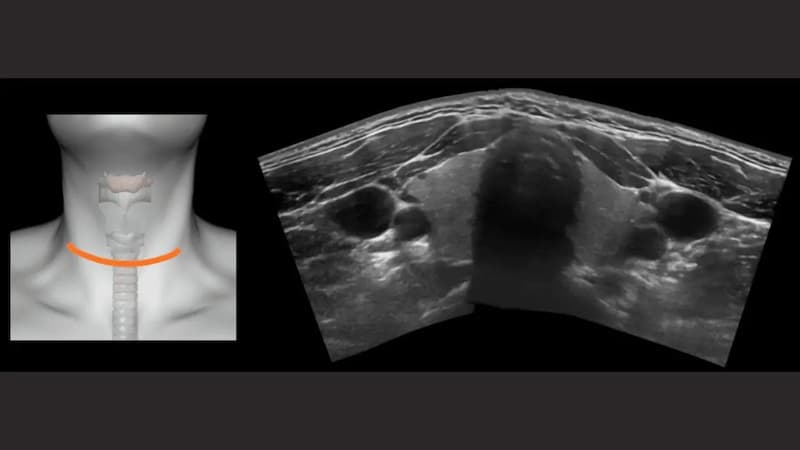

Siêu âm hạch vùng cổ là phương pháp sử dụng sóng siêu âm tần số cao để quan sát cấu trúc bên trong các hạch bạch huyết ở cổ. Đây là vị trí thường xuất hiện hạch liên quan đến nhiều bệnh lý như lao hạch, ung thư hạch hoặc hạch di căn. Nhờ khả năng hiển thị hình ảnh rõ nét, siêu âm giúp bác sĩ đánh giá chính xác hình dạng, kích thước, mật độ và vị trí của hạch, từ đó định hướng chẩn đoán sớm và phù hợp.

So với việc thăm khám bằng cách nhìn và sờ thông thường, siêu âm hạch vùng cổ có độ nhạy và khả năng phát hiện cao hơn nhiều. Phương pháp này có thể phát hiện cả những hạch rất nhỏ, đường kính dưới 2mm – điều mà chụp cắt lớp vi tính khó nhận ra nếu hạch nhỏ dưới 5mm. Khi kết hợp siêu âm Doppler, bác sĩ còn đánh giá được sự phân bố mạch máu trong hạch, hỗ trợ phân biệt hạch lành tính hay ác tính với độ chính xác cao.

Trong quá trình thực hiện, người bệnh nằm ngửa, cổ hơi ngửa ra sau, hai tay đặt xuôi theo thân mình. Đây là tư thế chuẩn trong quy trình siêu âm cơ phần mềm vùng cổ mặt nhằm giúp quan sát rõ toàn bộ hệ thống hạch cổ. Bác sĩ bôi gel lên vùng da cần khảo sát, sau đó di chuyển đầu dò nhẹ nhàng, quét lần lượt các nhóm hạch để tránh bỏ sót tổn thương.

Khi phát hiện hạch, bác sĩ sẽ đánh giá đầy đủ các tiêu chí theo quy trình siêu âm hạch vùng cổ Bộ Y tế, bao gồm:

- Vị trí và số lượng hạch.

- Hình dạng (bầu dục hay tròn).

- Kích thước, đặc biệt là đường kính trục ngắn và trục dài.

- Tỷ lệ giữa hai đường kính để gợi ý nguy cơ lành tính hay ác tính.

- Cấu trúc rốn hạch còn hay mất.

- Độ dày và tính chất vỏ hạch (đều hay không đều).

- Mức độ tăng sinh mạch máu qua Doppler màu.

- Các dấu hiệu bất thường như hoại tử, hóa dịch, vôi hóa.

Ngoài vùng cổ, bác sĩ cũng khảo sát thêm các vị trí lân cận, đặc biệt là hạch thượng đòn vì đây có thể là vị trí gợi ý bệnh lý ác tính.

- Hạch bình thường thường có hình bầu dục, trục ngắn dưới 10 mm, rốn hạch rõ, mạch máu phân bố trung tâm.

- Hạch viêm thường vẫn còn rốn hạch, có thể to nhưng hình dẹt hoặc bầu dục, tăng sinh mạch máu nhẹ.

- Hạch nghi ngờ ác tính thường tròn, vỏ dày không đều, mất rốn hạch, tăng sinh mạch máu ngoại vi, có thể kèm hoại tử hoặc vôi hóa.